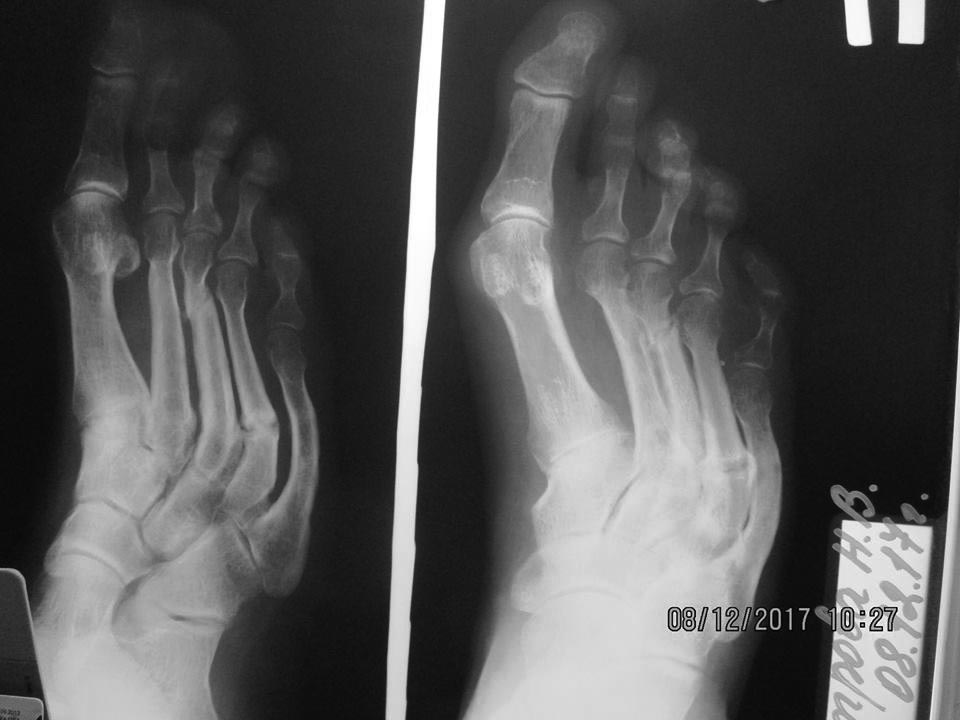

Пациентка 36 лет, несколько избыточного веса. За неделю до обращения почувствовала боль в правой стопе. В 2015 была аналогичная ситуация, тогда болевой синдром продолжался в течение 3-х месяцев. Местно: на тыльной поверхности переднего отдела - отёк, гиперемия и боль при пальпации; форма стоп – обычная. На рентгенограмме: перелом дистальной трети III-ей плюсневой кости со смещением, консолидированный перелом проксимальной трети IV-ой (V-ой?) плюсневой кости, дугообразная деформация III-V-ых плюсневых костей. От госпитализации отказалась. Наложена гипсовая лонгета, рекомендовано обратиться к эндокринологу (остеопороз?). Через 1,5 мес. – сращение перелома (рентгенография левой стопы – без особенностей). Лабораторное исследование у эндокринолога пока не выявило какой-либо патологии (УЗИ щитовидной и паращитовидных желез – 15.01.18).Три «незаметных» перелома! Что Вы думаете, господа, по этому поводу?

Интересная рентгенологическая картина! Стрессовые переломы различной давности... И все с одной стороны.

Понятно, что речь идет о стрессовых переломах. Если отсутствуют симптомы периферической нейропатии, то наиболее вероятная причина - врожденные (или приобретенные) особенности строения стопы. Провоцирующими моментами могут быть непривычные нагрузки (в отпуске на экскурсии ходила?), ходьба в обуви на плоской тонкой подошве, ношение тяжестей. Нужно тщательно собрать анамнез, может и найдется какое-то изменение привычного образа жизни перед появлением болей. К остеопорозу стрессовые переломы редко имеют отношение. А лечение вполне может проводиться по тем же принципам, что и ведение пациентов после не фиксированных остеотомий латеральных плюсневых костей: ранняя нагрузка в реабилитационной обуви на плоской ригидной подошве в расчете на то, что кость срастется в благоприятном для стопы положении. Степень разгрузки (костыли или трость) должна определяться только интенсивностью болевого синдрома. Гипсовая иммобилизация и костыли (особенно если пациент дисциплинированный) приводят к сращению кости в первоначальном положении. В результате перелом может рецидивировать.

Добрый вечер, очень похоже на Маршевую болезнь, (болезнь Дейчлендера). Чаще конечно бывает у срочников, но встречается данная патология и у женщин. Как правило, все начинается с болевого синдрома, рентген картина интактная, через 2 недели - рентгенологические признаки периостита, с последующим развитием стрессового перелома. Учитывая наличие старого перелома IV плюсневой кости - патологиеский процес перестройки костей стопы не завершен, возможны пояления новых стрессовых переломов. Причина- вялотекущий компартмент- синдром стопы из-за переизбыточной, длительной перенагрузки. Процесс запущен и классическая разгрузка стопы на 1,5 месяца недостаточна, необходимо соблюдать ограничение нагрузки на стопу как минимум 3-4 месяца, а то и полгода. В лечении: дезагреганты, спазмолитики, инфузионная терапия, физиотерапевтическое лечение- все, что мы используем при компартменте І степени. Рентген обоих стоп под нагрузкой для определения степени плоскостопия, коррекция ортопедическими стельками, коррекция веса. Есть докторская работа Савки И.С. где на клинических примерах использован хирургический метод лечения: фасциотомия пораженного футляра стопы, туннелизация плюсневой кости, металлоостеосинтез минипластиной, что сокращает длительность иммобилизации.Удачи!

Конечно, военный врач маршевую болезнь чаще встречает у срочников. А гражданский - у женщин 4-6-го десятков на приеме в поликлинике. Работа Савки И.С., на которую Вы ссылаетесь, как раз посвящена стрессовым переломам у военнослужащих. Представить, что алгоритм обследования и лечения, описываемый в диссертации, будет предложен пришедшей на прием в поликлинику пациентке сложно. Ведь согласно рекомендациям диссертации, при проксимальных и дистальных переломах плюсневых костей показано оперативне втручання в об’ємі: фасціотомія, деперіостеотомія і тунелізація зони перебудови та металоостеосинтез (к сожалению, на русском языке найти работу не удалось, хотя диссертация и была написана на русском). Как я написал в предыдущем сообщении, стрессовые переломы у попадающих на прием пациенток возникают на фоне врожденных или приобретенных деформаций стопы. В данном случае деформация костей очевидна. Представим, что в 2015 г. пациентке было бы выполнено вмешательство даже в минимальном объеме фасциотомии с последующей длительной разгрузкой и мощной медикаментозной терапией, о которой Вы пишете. Но деформация как реальная причина перегрузки, осталась бы. Насчет того, относятся ли основание 4-й и дистальный конец 3-й плюсневой к одному компартменту - не знаю. То есть, предотвратила бы та фасциотомия последующее повышение давления в соседнем компартменте? Так что если уж думать об операции - то с устранением деформации. Но в данном случае деформация уж очень сложная. И самый надежный и простой способ - ранняя нагрузка. Кстати, про 3-6 месячную разгрузку при стрессовых переломах стопы в диссертации я ничего не нашел.